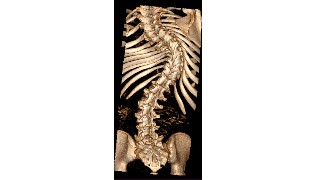

El Hospital Nuestra Señora del Rosario ha sido escenario de un nuevo hito médico, al acoger con éxito la primera intervención en la sanidad privada madrileña de corrección quirúrgica de escoliosis con tecnología 7D. Este novedoso navegador, que permite al cirujano, gracias a una recreación virtual de la columna del paciente, ser más preciso en la colocación de los tornillos correctores, reduciendo considerablemente los riesgos, ha sido incorporado por el equipo del Dr. Rafael González Díaz, jefe de la Unidad de Cirugía de Columna del centro.

Previamente a la operación, se realiza una TAC al paciente, prueba que sirve al sistema quirúrgico 7D para recrear virtualmente un mapa topográfico de su anatomía. A partir de ahí y de que el cirujano señale tres puntos de referencia, el dispositivo señalará la orientación exacta para la introducción de los tornillos pediculares. Este registro se ejecuta en unos pocos segundos por lo que se puede repetir sin interrumpir el flujo de trabajo quirúrgico. Además, el sistema se puede recalibrar rápidamente si se golpea la matriz de referencia o si la anatomía del paciente ha tenido movilidad, una característica que ningún otro sistema de navegación puede ofrecer en la actualidad.